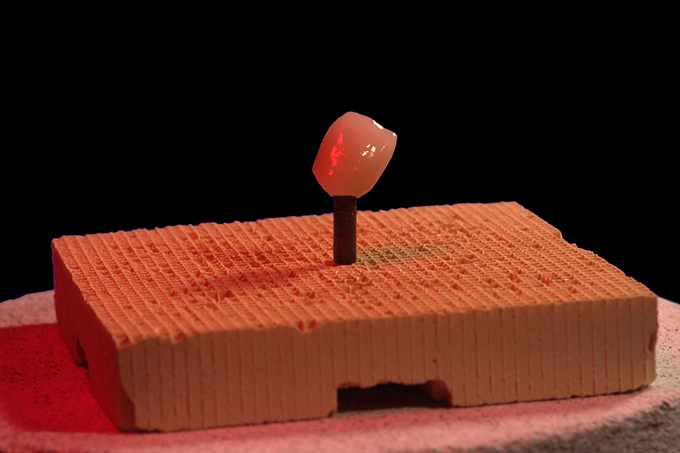

Fertiggestellte Krone.

Fertiggestellte Krone und VITABLOCS® TriLuxe.